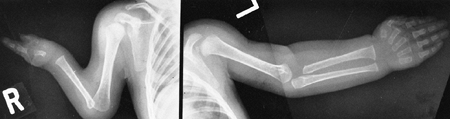

In each of these locations, there is a course similar to that in the

tibia, with bone loss and difficulty in achieving union (Fig. 9.13). Not all pseudarthroses of the forearm require treatment (122), but if they are symptomatic, the available options include proximal and distal synostosis to produce a single-bone

Figure 9.13

Neurofibromatosis in a 3-year-old patient. The radiograph shows progressive pseudarthrosis of the radius and ulna after a pathologic fracture. A: Fracture through the cystic lesion of the radius and thinning of the mid-ulna. B: After 10 months of cast immobilization, pseudarthrosis affects the radius and ulna. (From Goldberg MJ. The dysmorphic child: an orthopedic perspective. New York: Raven Press, 1987, with permission.) |